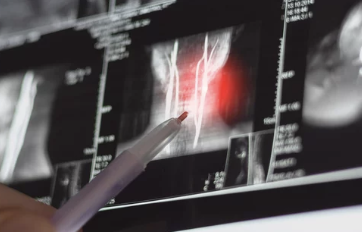

1. 목디스크란 무엇인가?

목디스크의 정의

목디스크(경추 추간판 탈출증)는 목뼈 사이에 있는 디스크(추간판)가 탈출하거나 찢어져 신경을 압박하는 상태를 말합니다. 이로 인해 통증, 저림, 움직임 제한 등이 발생합니다.